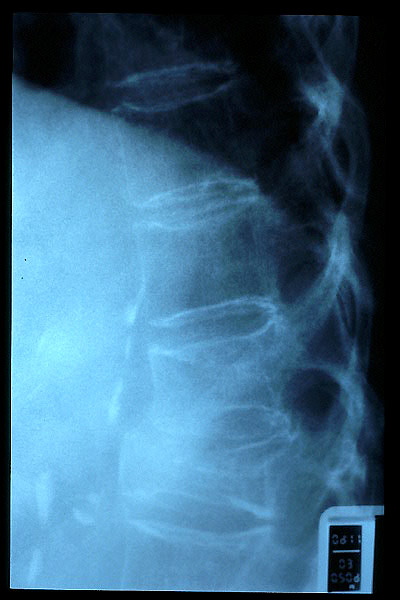

Osteoporosis. Cifosis.